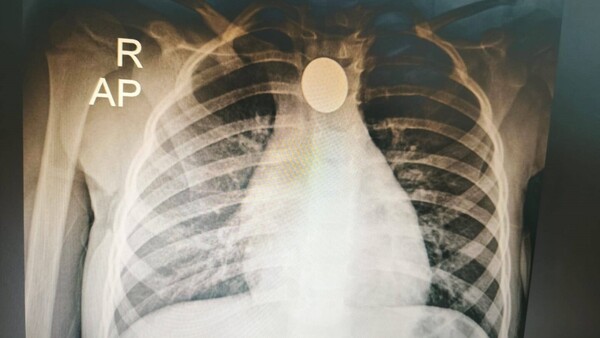

Médicos del Ineram salvan la vida a una niña de tres años que tragó una moneda

Una niña de tres años oriunda de Mariano Roque Alonso fue intervenida de urgencia tras tragar una moneda. El objeto extraño fue extraído gracias a la pericia de médicos del Instituto Nacional de Enfermedades Respiratorias y del Ambiente (Ineram). ...[Leer más]